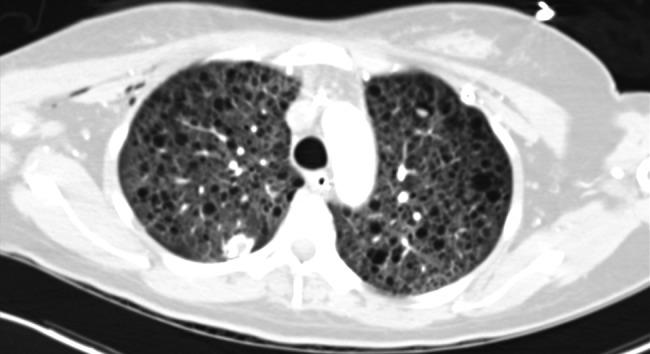

Gestational acute respiratory distress syndrome (ARDS) is a complicated problem with the potential to gravely harm both mother and fetus. This case report describes a young woman in her second trimester of pregnancy who developed progressive respiratory failure in the setting of newly diagnosed influenza, diffuse alveolar hemorrhage and lymphangioleiomyomatosis. The patient's condition was refractory to conventional interventions and required extracorporeal membrane oxygenation (ECMO) support. Her course was further complicated by preeclampsia requiring preterm delivery with cesarean section while on ECMO. Through novel therapies and a multidisciplinary approach to care, both the patient and her child would overcome these unique and challenging conditions and survive.

妊娠急性呼吸窘迫综合征(ARDS)是一个复杂的问题,有可能严重伤害母亲和胎儿。本病例报告描述了一名处于妊娠中期的年轻女性,她在新诊断出流感、弥漫性肺泡出血和淋巴管平滑肌瘤病的情况下出现进行性呼吸衰竭。患者的病情对传统干预措施无效,需要体外膜肺氧合(ECMO)支持。她的病情因子痫前期而进一步复杂化,在接受ECMO治疗期间需要剖宫产提前分娩。通过新颖的治疗方法和多学科护理方法,患者和她的孩子都克服了这些独特且具有挑战性的情况并存活下来。